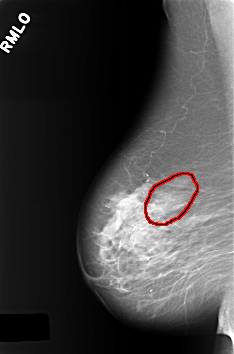

C_0391_1.RIGHT_MLO

FILE: C_0391_1.RIGHT_MLO.OVERLAY

TOTAL_ABNORMALITIES 1

ABNORMALITY 1

LESION_TYPE CALCIFICATION TYPE PUNCTATE DISTRIBUTION SEGMENTAL

ASSESSMENT 4

SUBTLETY 2

PATHOLOGY BENIGN

TOTAL_OUTLINES 1

BOUNDARY